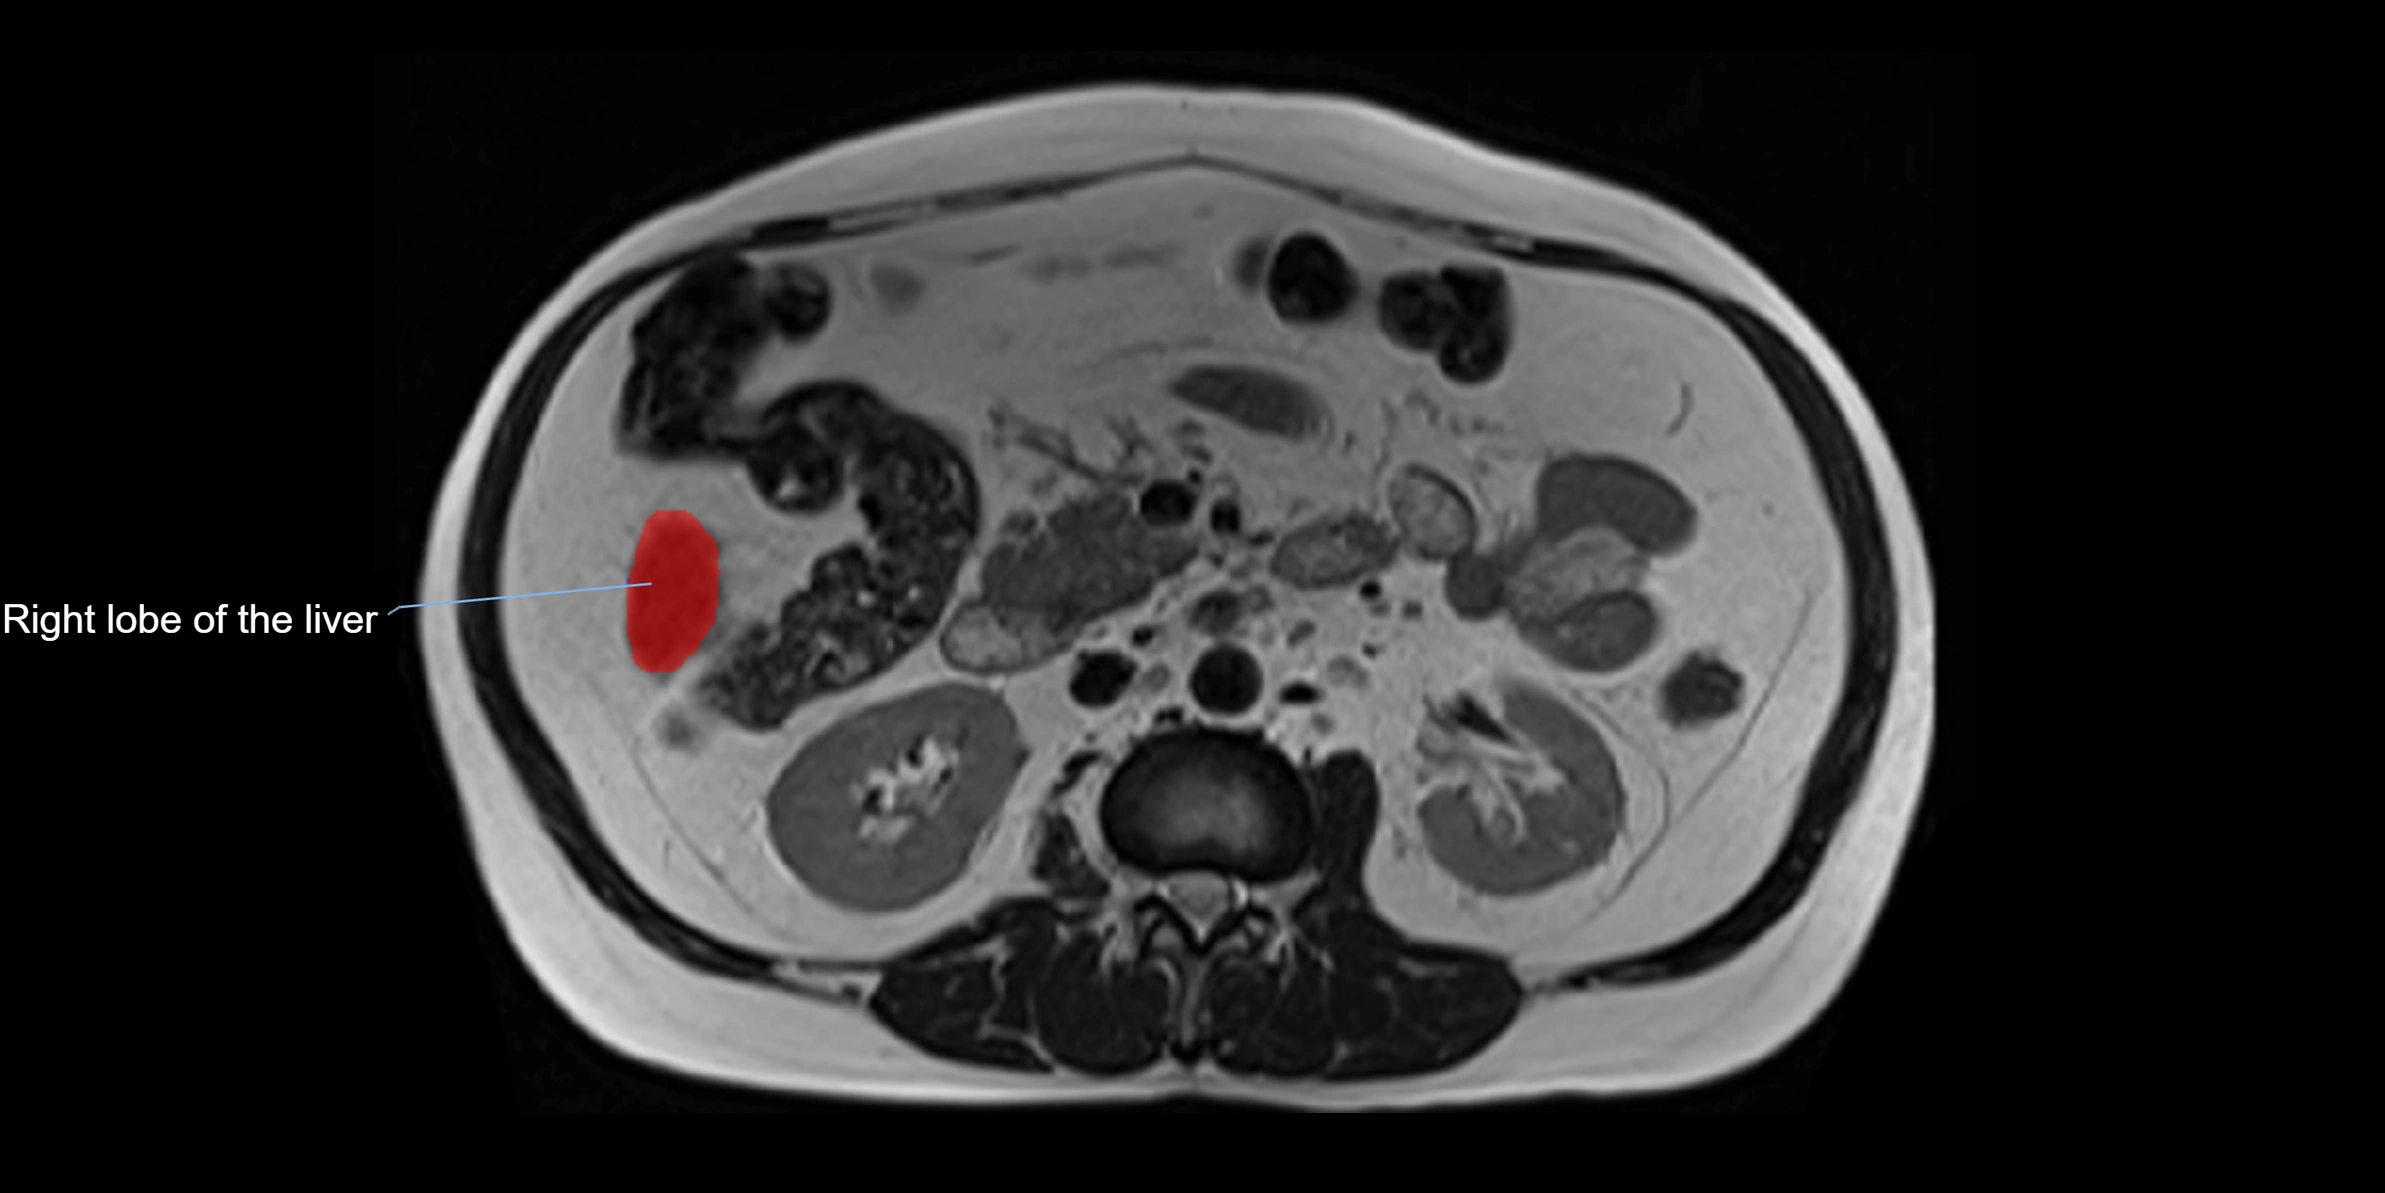

MRI image

image